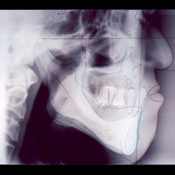

サージカルステントガイドに金属球を埋め込んだものを口腔内へ装着したときのレントゲン写真。上下の位置関係とインプラント埋入位置の確認を行います。サージカルステントガイドは実際のインプラント埋入手術の時、インプラント埋入のガイドとして使用される大切なものです。

装着後のレントゲン写真

患者様の横顔の写真をみると、上下のインプラントとその上部人工歯との関係がよくわかります。

上下顎で合計16本のインプラントを埋入しました。